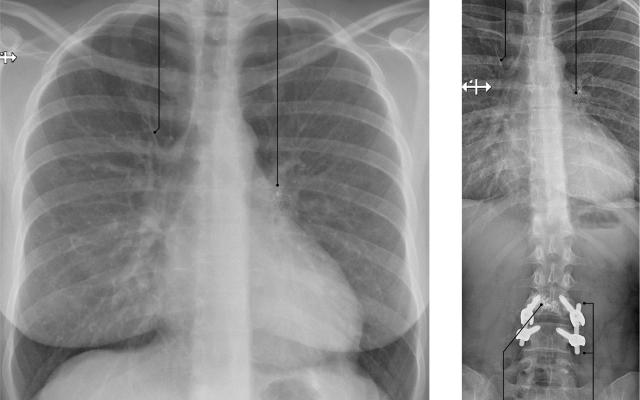

Dit artikel is alleen beschikbaar als PDF.Lees de PDF Artikelinformatie Online verschenen op 7 april 1960 Citeer dit artikel als Ned Tijdschr Geneeskd. 1960;104:1651-7 Heb je nog vragen na het lezen van dit artikel? Check onze AI-tool en verbaas je over de antwoorden. ASK NTVG Ook interessant Nieuws Spondylitis Diagnose in beeld Een vrouw met pulmonale klachten na re-spondylodese Onderzoek Spondylodiscitis bij spondylitis ankylopoetica Meer gerelateerd … Reacties Login om een reactie te plaatsen